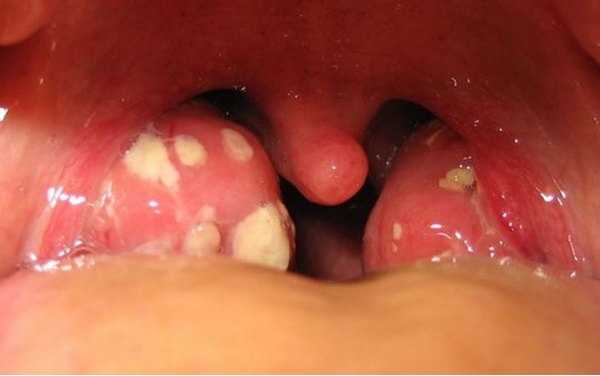

Тонзиллит – это общий собирательный термин, образованный от латинских корней, употребляемый в практической медицине для обозначения воспалительного процесса на одной или нескольких миндалинах. Миндалины – неотъемлемая часть лимфатической системы человеческого организма, которая одновременно входит в состав системы иммунной.

У взрослых и детей тонзиллитом называют ангину, однако такое наименование не совсем корректно, если вспомнить, что причинами появления воспалительного процесса могут быть, как внутренние, так и внешние причины.

Причинами перехода болезни в хроническую стадию могут выступать вариабельные факторы – постоянно присутствующие воспалительные процессы в этой области, не получившие достаточно эффективного лечения, инфицированием слизистой при других инфекционных заболеваниях, далеко не безобидных – скарлатине, дифтерии, кори. В последнем случае симптомы острой стадии могут не проявляться, а если развивается простая форма, то манифестируют только местные симптомы.

Название компенсированный в анамнезе свидетельствует о сохраненной защитной функции миндалин, процесс протекает локализовано и не поражает остальное пространство. При декомпенсированном тонзиллите у взрослых, симптомы присутствуют и местные, и указывающие на другие заболевания – паратонзиллит, гнойное воспаление, абсцесс. Это происходит из-за тотального поражения, в результате которого миндалины не выполняют защитную функцию, предусмотренную природой.